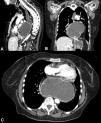

A 70-year-old woman had a past medical history of mixed large and small cell neuroendocrine carcinoma, with a focal component of endometrial adenocarcinoma that metastasized to the lung, as well as a history of a large hiatal hernia (>5 cm) (Fig. 1). She was admitted to the emergency department due to oppressive chest pain, radiating into the neck, that was exacerbated with food intake. Laboratory work-up reported leukocytes 21.3 × 109/L, neutrophils 18.3 × 109/L, C-reactive protein 37.8 mg/dL, lactate dehydrogenase (LDH) 241 IU/L, and lactate 2.7 mmol/L. Cardiac evaluation showed no alterations and angiotomography was negative for pulmonary thromboembolism but revealed an “hourglass” hiatal hernia (Fig. 2). Decompression was carried out with a nasogastric tube, and due to suspected gastric strangulation, the patient underwent hiatal hernia reduction and laparoscopic gastropexy, resulting in pain improvement. Hiatal hernias are divided into four types, the most complex of which are the paraesophageal hernias (types III and IV), accounting for 5–10% of cases (Fig. 3). In addition to the stomach, this type of hernia can contain parts of other abdominal viscera, such as the colon, small bowel, pancreas, or spleen. Acute complications of strangulation or ischemia warrant immediate decompression.

Multidetector computed tomography with intravenous contrast and multiplanar reconstruction, identifying the presence of the body and fundus of the stomach at the intrathoracic level secondary to a paraesophageal hernia, with important distension of the gastric chamber and esophagus (A) sagittal reconstruction; B) coronal reconstruction; C) axial view).